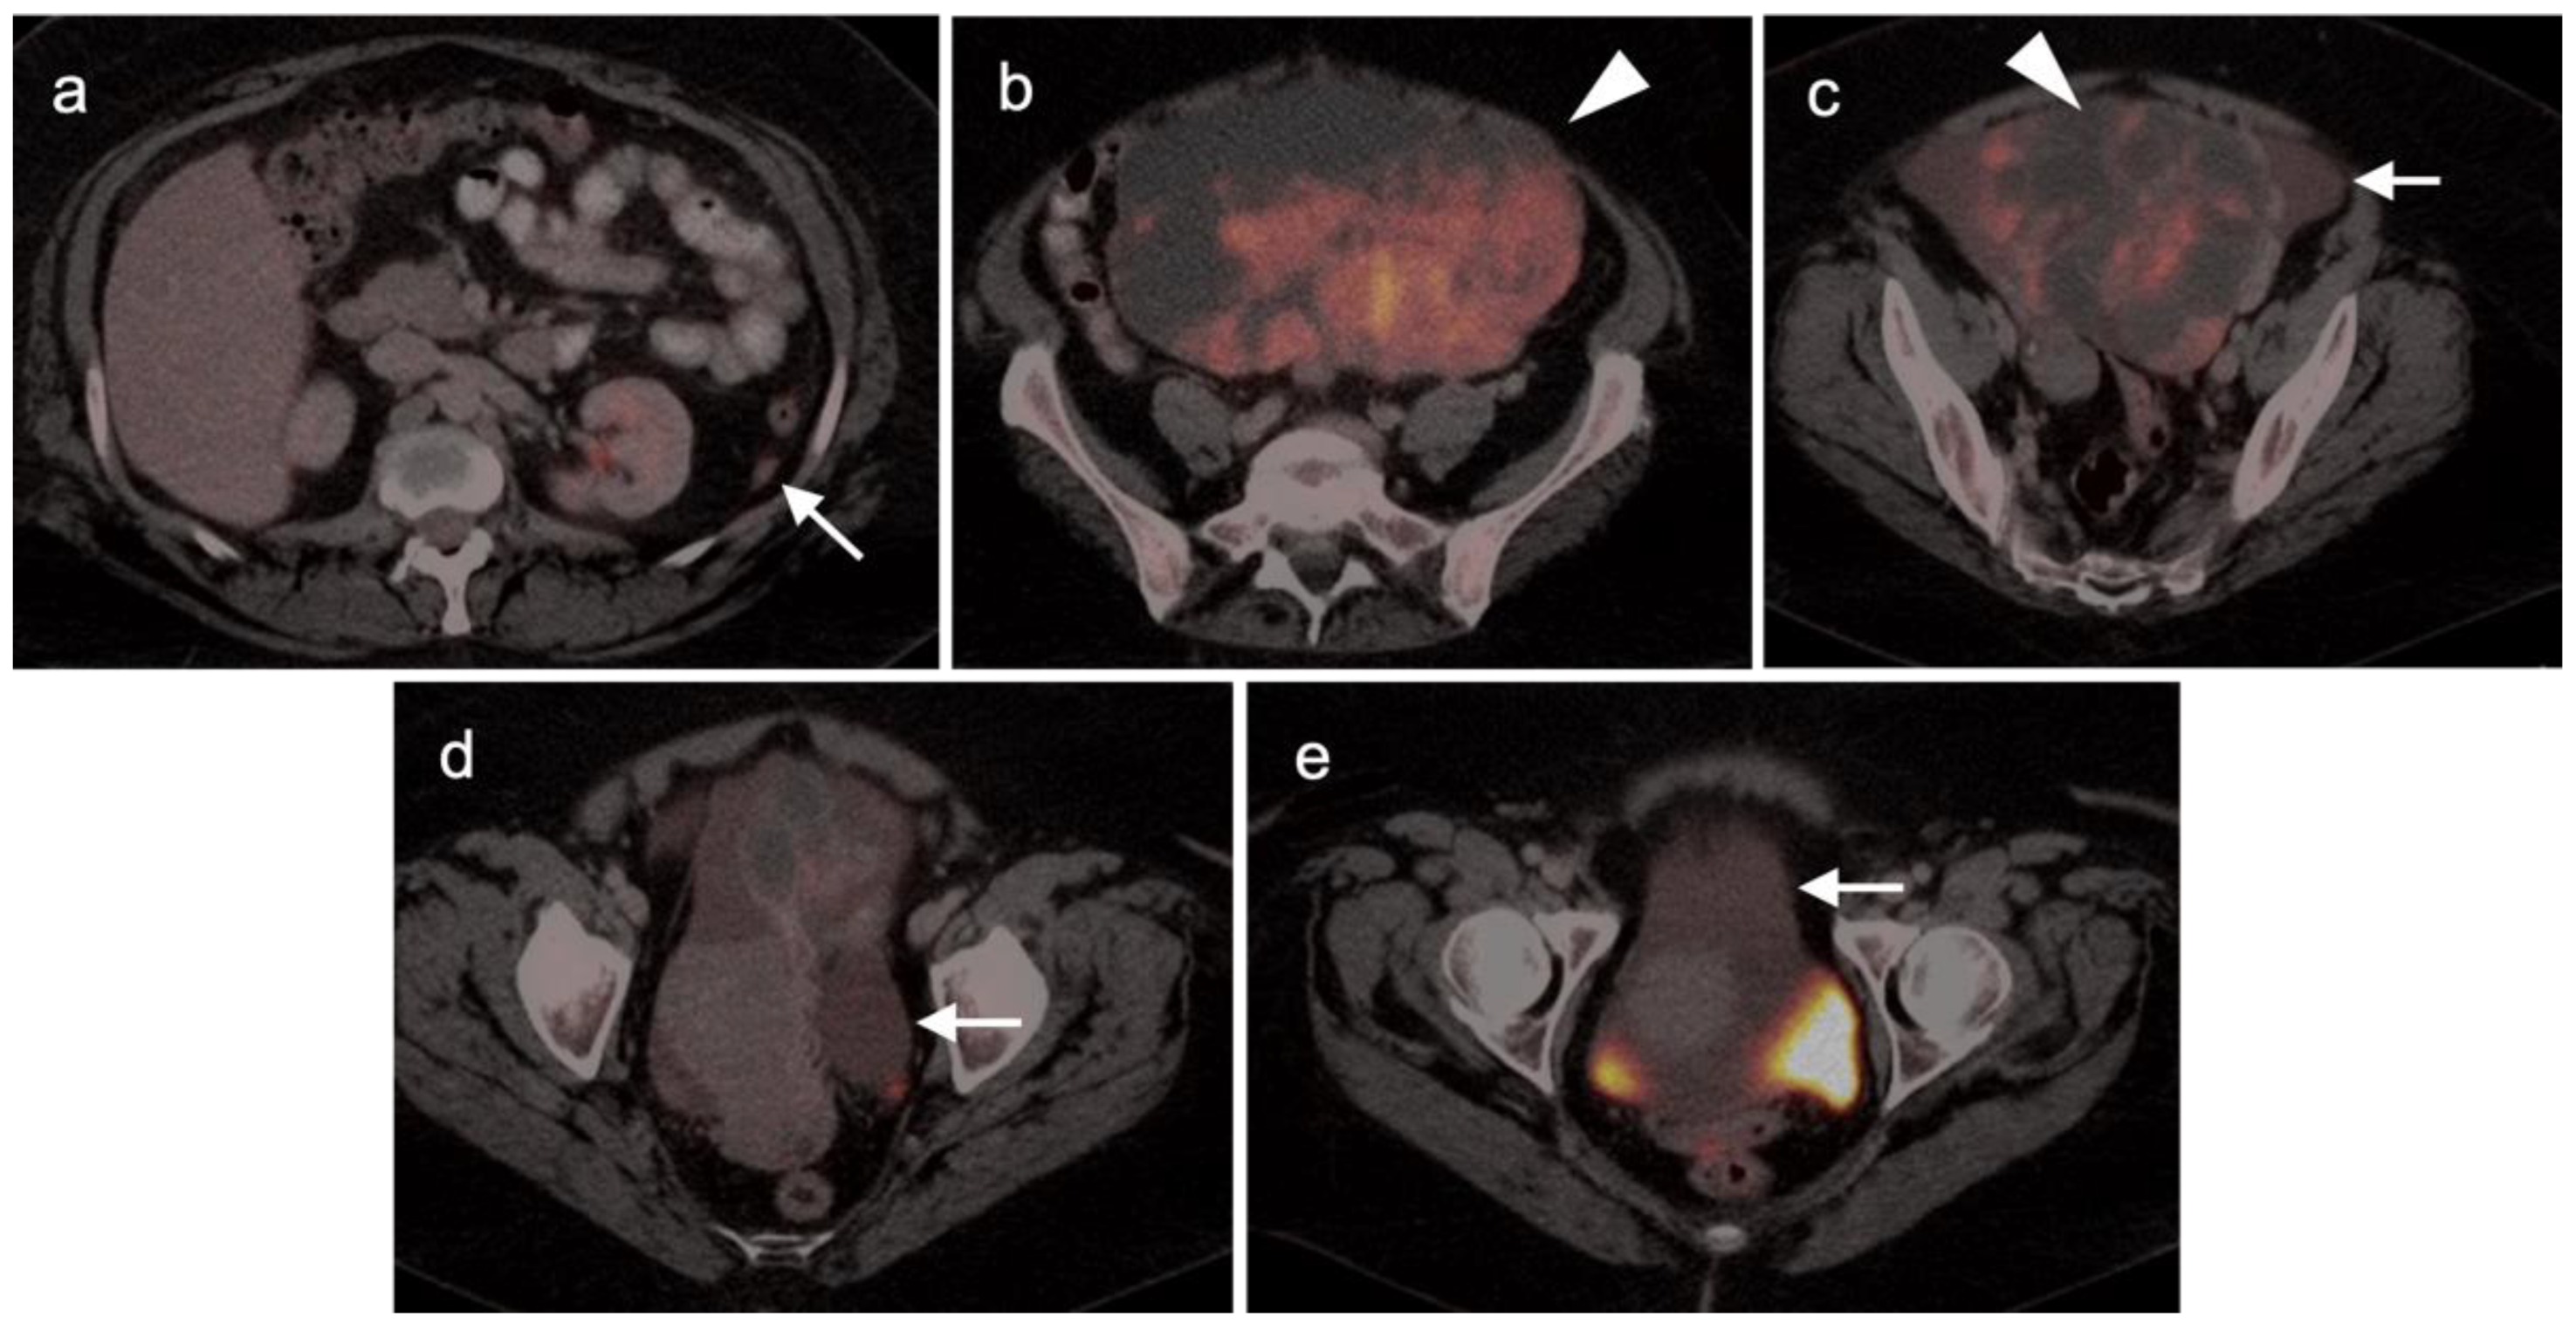

2.3. Uterine Neoplasms: Endometrial Carcinoma, Uterine Sarcoma and Leiomyoma

2.3.1. Endometrial Carcinoma

2.3.2. Uterine Sarcoma